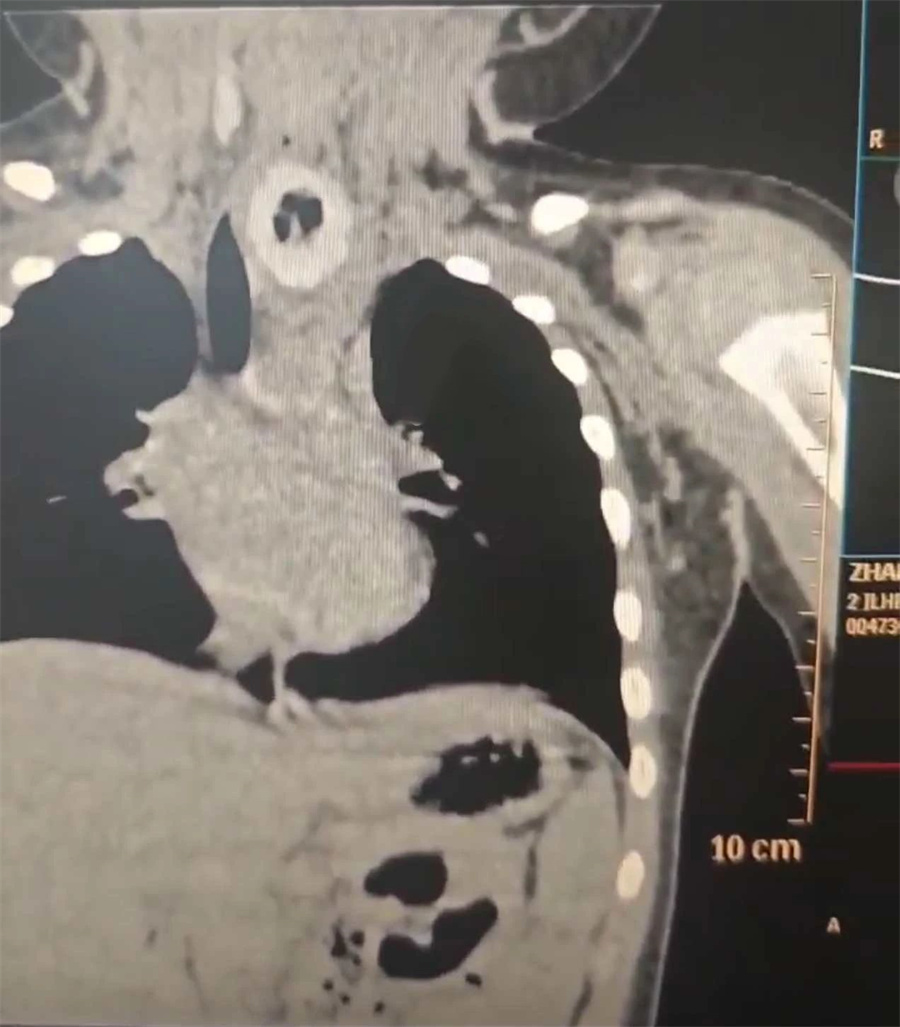

耳鼻喉科门诊医生仔细询问病史,了解到牛牛呕吐物为胃内容物、无血性物。胸部检查结果:双肺纹理增强,气管略向右偏移。结合症状和检查结果,初步诊断为食管内异物。随即安排牛牛入院作进一步治疗。

术中,杨小健副院长将食管镜沿患儿咽后壁置入,很快在距门齿约11cm处食道入口下方,发现一个较大的黄色不规则异物。异物周围黏膜已出现充血肿胀。

困扰牛牛呕吐、呛咳的“元凶”终于被消除了。随后,杨小健副院长再次置镜,在Hopkins镜引导下仔细查看,发现异物嵌顿处有黏膜溃疡破损,所幸无肉芽增生、明显穿孔及出血情况。整个手术过程非常顺利,仅用时10分钟。考虑到异物带来的后续缓慢性损伤,术后,团队对牛牛采取禁食水、抗感染及补液等对症支持治疗。